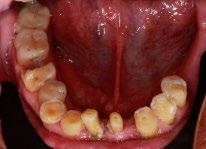

En los estudios intraorales, las fotografías iniciales muestran clase I canina y molar bilateral, mordida anterior abierta, apiñamiento leve superior e inferior, y líneas medias dentales

desviadas. En las Figuras 4, 5 y 6 se observa la forma de las arcadas superior e inferior.

Figura 6. Oclusal superior e inferior de inicio.